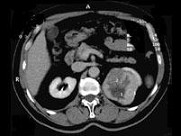

- 多项选择题男,65岁, 左侧腰背部胀痛伴无痛性全程血尿3月余,CT平扫及增强检查如图所示, 下列说法正确的是 ( )

A、平扫时见左肾上极有一软组织肿块影,其边界较清楚

B、增强扫描肾皮质期可见肿块明显强化,其内亦有无强化区

C、增强扫描肾实质期可见肿块强化迅速下降,但密度比平扫时仍要高

D、考虑为左侧肾癌

E、考虑为左侧肾错构瘤